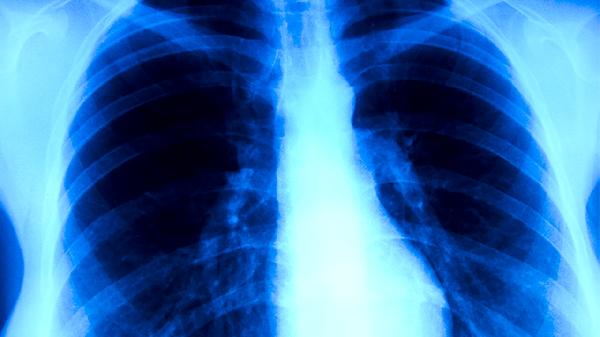

水飞蓟素具有抗氧化和抗炎作用,能减轻肝细胞氧化应激损伤,抑制肝脏纤维化进程。临床常用于非酒精性脂肪性肝炎患者的辅助治疗,可改善肝脏超声影像学表现。对药物性肝损伤也有保护作用。